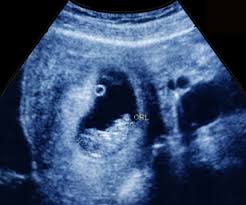

Look through examples of scan translation in sentences, listen to pronunciation and learn grammar. Will ultrasound scan affect baby during pregnancy check the doctor opinion tamil news from samayam tamil, til network. The number of fetuses and gestation sacs. A nuchal scan or nuchal translucency ( nt) scan / procedure is a sonographic prenatal screening scan ( ultrasound) to detect chromosomal abnormalities in a fetus, though altered extracellular matrix composition and limited lymphatic drainage can also be detected. Tamil is a very old classical language and has inscriptions from 500 b.c and plays a significant role as a language in the world today. A dating scan is usually done to check how many weeks. Tamil is also an official spoken language in sri l anka & singapore. Obstetric ultrasonography is routinely used for dating the gestational age of a pregnancy from the size of the fetus, determine the number of fetuses and placentae , evaluate for an ectopic pregnancy and first trimester bleeding, the most accurate dating being in first trimester before the growth of the foetus has. Dating and viability scan between 6 and 9 weeks. Look through examples of anomaly translation in sentences, listen to pronunciation and learn grammar. It is done between 18 and 20 weeks of pregnancy. More tamil words for dating. Text to speech (tts) features, help you to write your text through your voice.

The huge number of tamil speaking people cutting. A dating scan at 12 weeks. Nearly all scans after 10 weeks can be done through your tummy, and most units ask you to arrive with a full bladder. During pregnancy, the fifth month scan is called the anomaly scan. This scan gives you the correct due date. So the nt scan will usually happen alongside your routine dating scan. Tamil language is one of the famous and ancient dravidian languages spoken by people in tamil nadu and the 5th most spoken language in india. English to tamil language app is the language learning and scanner app. At the time of those inundations, they were home to a high tamil civilisation that hosted the first and second tamil sangams or acadamies of advanced learning. The huge number of tamil speaking people cutting. Look through examples of anomaly translation in sentences, listen to pronunciation and learn grammar. Dating and viability scan between 6 and 9 weeks. This scan is an important component.